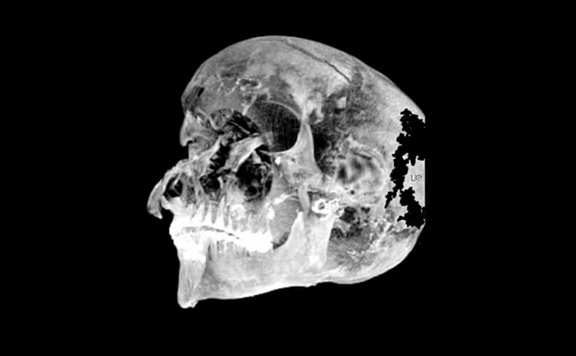

جمجمة الفرعون Sekenenra Taa II

تصوير مقطعي لرأس الفرعون سكنينر تا الثاني. يظهر أن الدماغ ينزح إلى جانب واحد من الجمجمة.